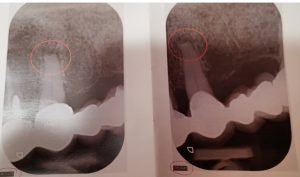

Apikotomija je oralno-hirurška intervencija koja se izvodi u lokalnoj anesteziji, prilikom koje se odstranjuje vrh korena zuba uklanjajući istovremeno i patološki proces koji se na njemu stvorio. Ovim postupkom moguće je sačuvati zub, odnosno izbeći vađenje.

Patološki proces na vrhu korena zuba najčešće se formira kao posledica uznapredovalog karijesa i inficiranog zubnog živca ili kao posledica traume.

Procesi na vrhu korena zuba predstavljaju infektivno žarište, koje se najčešće aktivira padom imuniteta kod pacijenta izazivajući pojavu bola, otoka i povišene temperature. Dijagnoza se postavlja na osnovu simptoma pacijenta, kliničkog pregleda i rendgenskog snimka.

Nakon adekvatne preoperativne pripreme i anesteziranja operativnog područja, hirurški se pristupa inficiranom vrhu korena zuba i odstranjuje se proces. Intervencija je bezbolna i traje u proseku 30 minuta. Nakon operacije, neophodno je pridržavati se uputstva stomatologa, kako bi oporavak bio što kraći i lagodniji. Konci se uklanjaju sedam do deset dana od operacije.